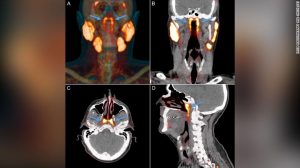

Un grupo de científicos de Países Bajos, han descubierto un par de glándulas que están escondidas en el cráneo humano donde se encuentra la cavidad nasal y la garganta. Esto durante una exploración diseñada para buscar crecimientos tumorales.

Esta “identidad desconocida” solo se logró captar cuando los doctores utilizaron un tipo de exploración nuevo llamado PSMA PET/CT que se ha aplicado para detectar la propagación del cáncer de próstata.

Las “glándulas tubarias” recientemente descubiertas hicieron que se armara un debate en cuanto a si se trata de un nuevo órgano o si podían considerarse parte del sistema de órganos de las glándulas salivales.

Sin embargo, el estudio arrojó que “estos hallazgos apoyan la identificación de las “glándulas tubarias” como una nueva entidad anatómica y funcional”.